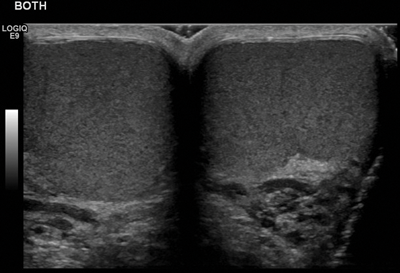

Figure 2: Transverse section through the midline showing both testes are of the same echogenicity.

Both testes should be compared in the transverse plane, as the testes should be of a similar size and echogenicity (Figure 2) and direct comparison between the two testes is advised as part of routine ultrasound.